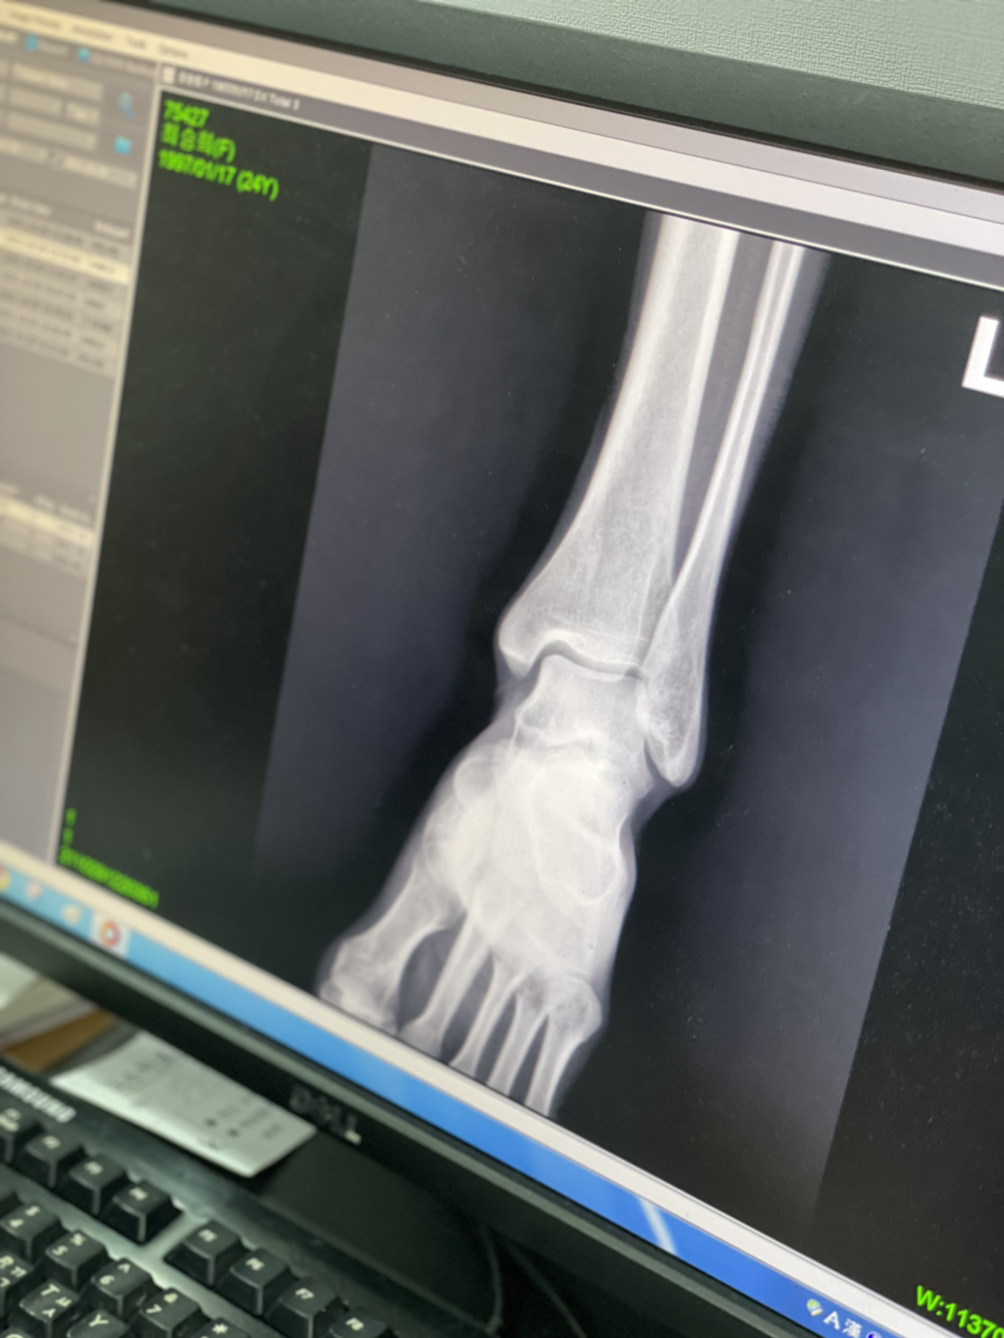

아플땐 쉬어가자 ㅎ ..아킬레스건염이라네..^^..

골반이 삐뚤어졌대

종형외과...

넘비싸...8ㅅ8 근데 너무아프고...ㅋㅋㅋ 많이 삐둘어지긴한듯